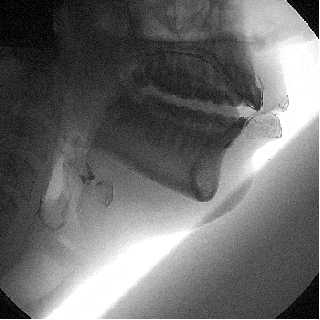

ニック・ロッシーノが液体バリウムを飲み込むところ。 バリウムを飲んでX線を当てると液体が見える。このビデオでは液体が全部飲み込まれず、ロッシーノの喉に一部たまっているのがわかる。

こちらのビデオは嚥下障害に苦しむ患者の嚥下造影の様子。